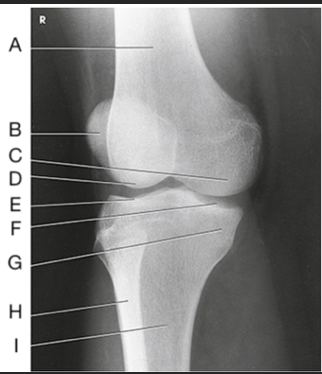

Name this projection.

AP oblique lateral rotation

What is demonstrated?

Medial aspect (distal femur, patella, medial tibial condyles, and fibula)

Label the image: A

femur

Label the image: B

patella

Label the image: C

medial femoral condyle

Label the image: D

lateral femoral condyle

Label the image: E

Lateral tibial plateau

Label the image: F

medial tibial plateau

Label the image: G

medial tibial condyle

Label the image: H

fibula

Label the image: I

tibia